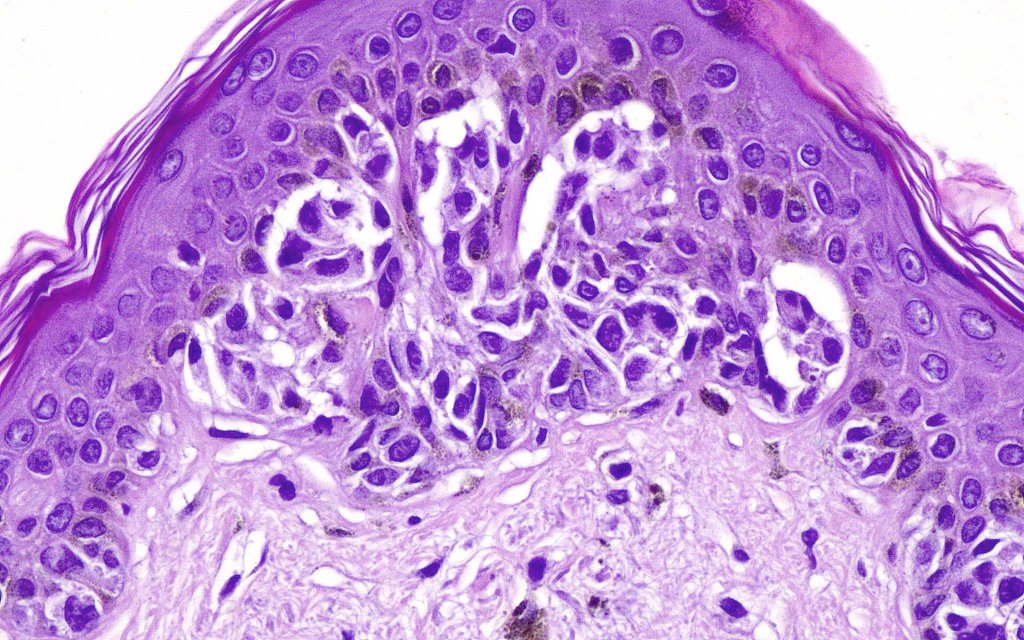

2. Melanocytes generally small, epithelioid (rather than spindled) with either vesicular nuclei and prominent nucleoli or are hyperchromatic.

3. The cells can be present singly, in short pallisades or can extend along a large section of epidermis

4. Pagetoid spread is sometimes seen in more established lesions

6. Mitoses are not conspicuous